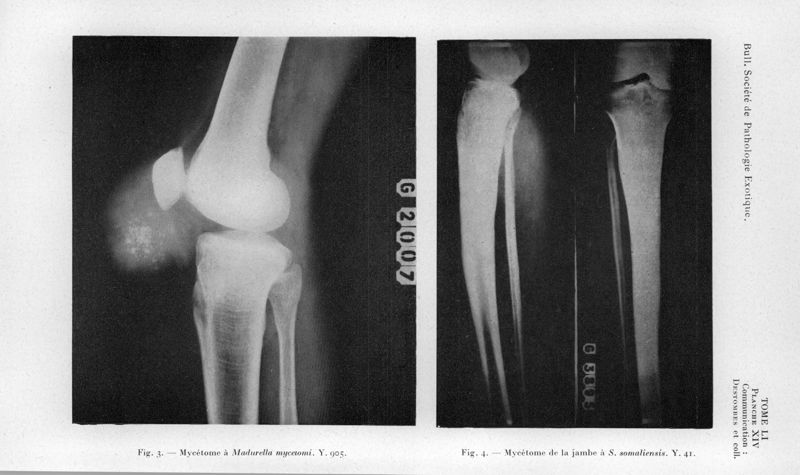

Bulletin de la Société de pathologie exotique et de ses filiales

1958, tome 51. - Paris : Masson, 1958.